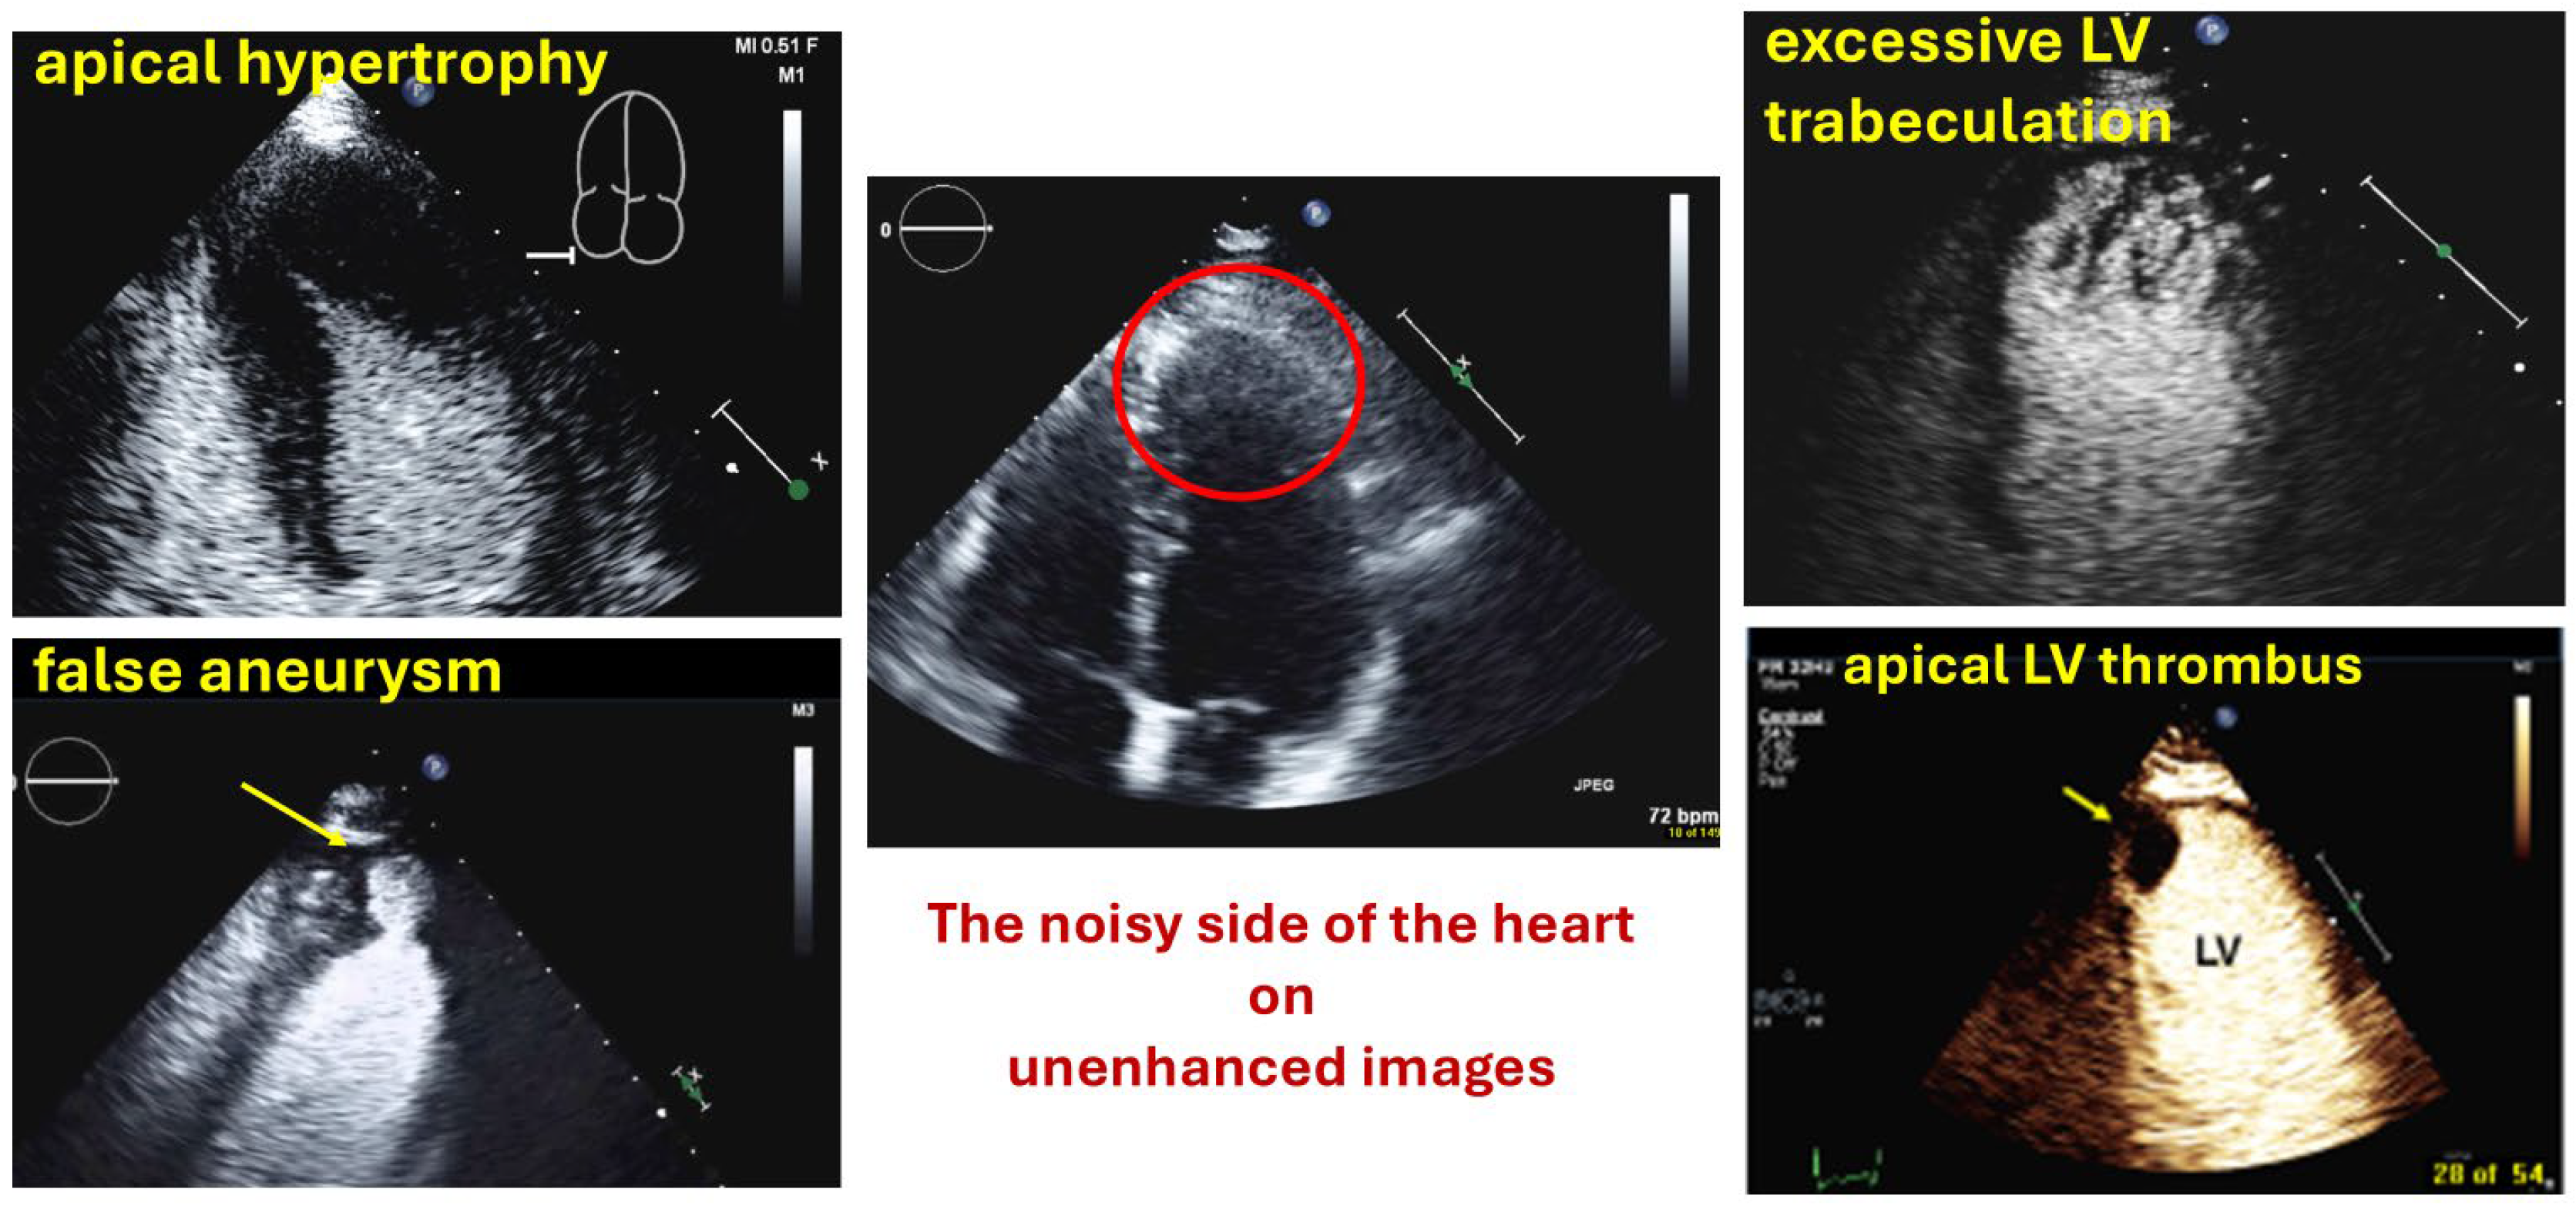

| Myocardial disease and masses |

| Thrombi |

| Apical hypertrophy |

| Pseudoaneurysm |

| Excessive LV trabeculations |

| Typical findings | Clear demarcation from the normal myocardium Narrow neck of false aneurysms Search for associated thrombi and pericardial effusion (more likely near false aneurysms) |

| Typical finding | 1. Hourglass/ace-of-spades shape of apical LV cavity 2. Apical myocardium appears dark in late systole due to compression of the intramyocardial vessels 3. Apical aneurysms +/− thrombi in some patients |

| Typical findings | trabeculated layer apical, lateral, and inferior: more than 3 trabeculations, ratio of trabeculated/compact myocardium >2 The number of trabeculations and the ratio of trabeculated/compact myocardium does not seem to impact clinical management |